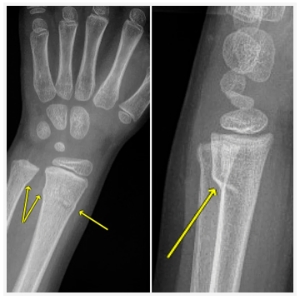

Buckle fractures occur typically in youth athletes under the age of 13- most commonly between the ages of 5 and 10. The bones at this age are not fully developed in the wrists, so, in the event of a fall, the bone actually buckles or folds.

A F.O.O.S.H. in adults can result in a fracture or a break, but, for children, the bones in the wrist are not fully developed. Sometimes, this means that, instead of a fracture or a break, a less traumatic fracture–a buckle fracture–occurs. The bones, instead of breaking under the pressure of a fall, fold. This doesn’t mean that more traumatic injuries never happen when a F.O.O.S.H. occurs, but your kids are really resilient, and so are their bones!